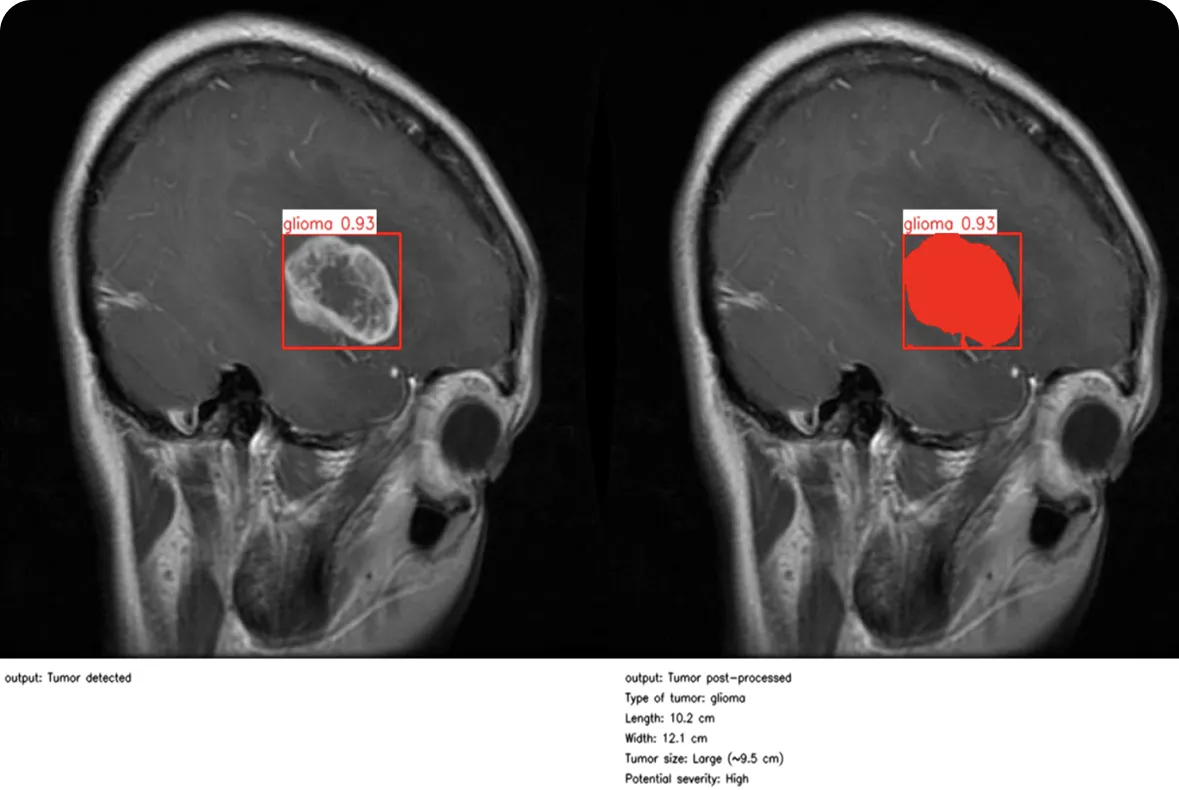

Similarly, healthcare is seeing major advances as computer vision becomes part of everyday clinical workflows. In medical settings, precision and timing are critical, and computer vision research and AI-driven image analysis are letting clinicians make faster, more informed decisions.

This is true across many areas of healthcare. Take ophthalmology, for example. At Moorfields Eye Hospital in the UK, researchers developed RETFound, one of the first AI foundation models in medicine and the first in eye care.

Trained on 1.6 million retinal images using self-supervised learning, the model can detect sight-threatening conditions such as diabetic retinopathy and glaucoma, and even predict broader systemic diseases like heart failure, stroke, and Parkinson’s based on subtle retinal clues.